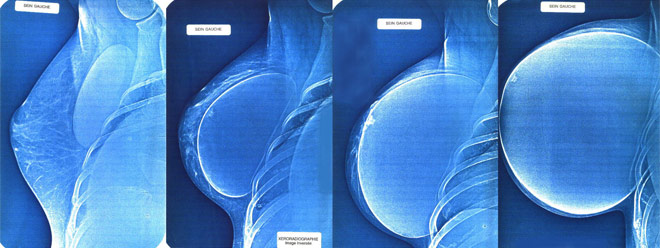

Minka tiene implantes de seno de polipropileno o expandibles, también utilizados por estrella de busto aumentado como Chelsea Charms y Maxi Mounds (entre otras) logran tamaños excepcionalmente grandes de busto. Minka tiene un tamaño copa de sostén reportado como 44KK. Ella afirma que sus senos pesan 13,5 libras cada uno. Ella esta casada con su antiguo manager, “Woody”, quien fue su pareja principal en la mayor parte de sus películas adultas caseras.

Chelsea es más conocida por sus senos sumamente grandes, ciertamente entre las más grandes del mundo, lograda a través del uso de implantes de seno de fibra de polipropileno.

En su página Web oficial Chelsea dice que su tamaño del busto es 153XXX, y que sus senos pesan 26 libras cada uno. Debido a la naturaleza de de fibra de polipropileno, los pechos de Chelsea se están extendiendo continuamente (aproximadamente 25 milímetros por mes), por lo que tiene que acudir con regularidad a su cirujano en Houston, para que le drene el liquido excedente que sea necesario.

Chelsea tenía una copa D natural y empezó desarrollándose en la cuarta categoría. Se ha operado tres veces. La primera le agrandó a una copa E. La segunda a una copa HH. Las dos eran bolsas salinas. La tercera cirugía implantó la fibra de propileno. En algunos casos de aumento de senos vía método del propileno, los pechos pueden crecer a pasos diferentes o a una proporción peligrosamente acelerada. En su caso, sus senos han crecido al mismo tiempo, pero su proporción de crecimiento se ha retardado firmemente durante los años. El volumen de la fibra inicial era equivalente a 2500cc. Su doctor estimaba que el crecimiento ha aumentado el tamaño de cada seno por encima de 7000cc. Durante algunas apariciones más o menos recientes en festivales eróticos en Estados Unidos, Chelsea se presentó con 10.000cc batiendo así todas sus marcas.

Maxi tiene injertos de seno de fibra de polipropileno que son utilizado también por Chelsea Charms, Melonie Charm, y Minka para lograr unas medidas de senos imposibles. Los senos de Mounds pesan 9.07 Kg cada uno.